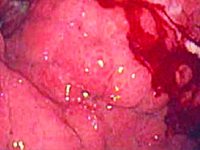

GinekologiaRakowiaki wyrostka robaczkowego są złośliwymi nowotworami - w większości przypadków diagnozowane przypadkowo u pacjentów poddanych appendektomii z innych przyczyn, a ze względu na ich niewielkie rozmiary, przedoperacyjna diagnoza jest w większości przypadków niemożliwa. Rakowiaki mogą powodować ostre zapalenie wyrostka robaczkowego w wyniku zatkania światła wyrostka.